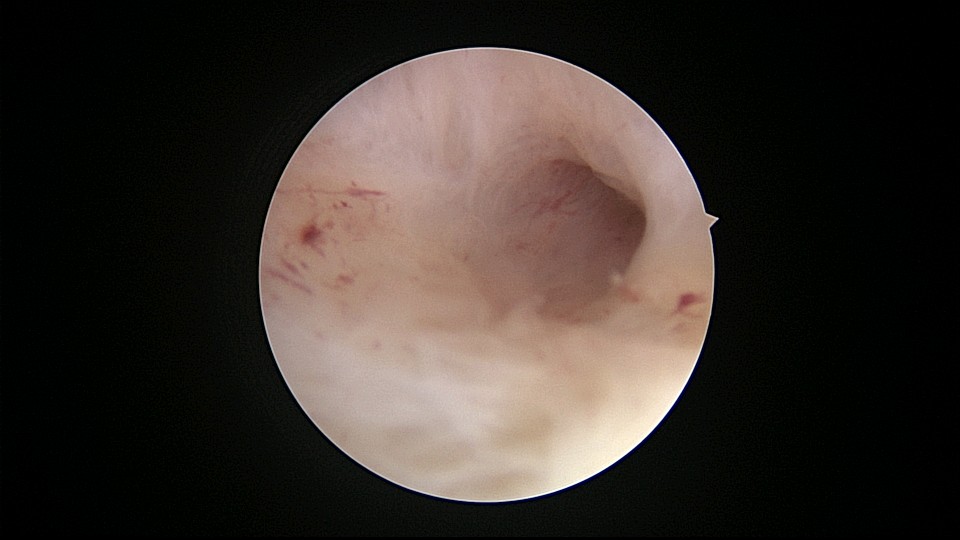

患者56岁,G2P1,剖宫产1次。安环30年,绝经7年,外院取环失败,形成假道。子宫后倾后屈位,宫颈外口萎缩狭小,宫颈管扩张膨大,宫颈管左前壁假道,宫颈内口狭窄坚硬,宫腔镜见宫腔偏向右后方,并向左后侧屈,镜子艰难进入宫腔,O型环位置正常,异物钳取出,宫腔无其他异常。